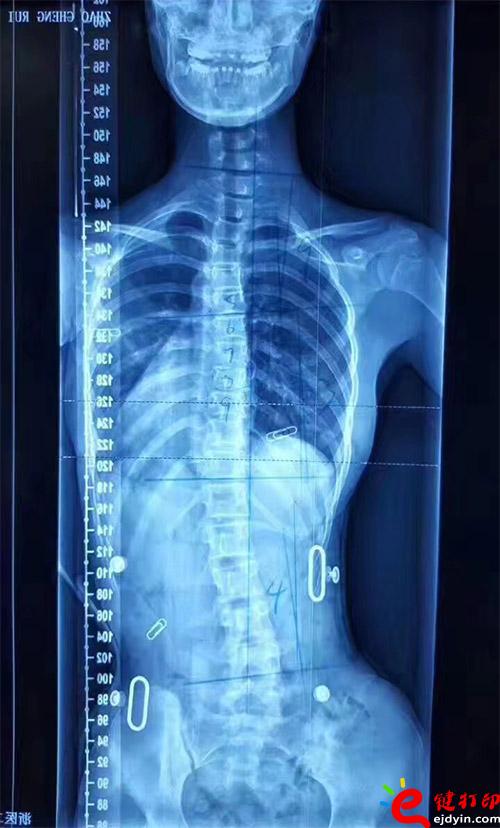

在脊柱侧弯患者中,仅有10%的青少年特发性脊柱侧弯患者最终需要手术治疗,90%的患者可以保守治疗和积极观察。非手术治疗中公认最主要和可靠的方式是用矫形支具治疗。像上图这样的案例就可以通过矫形器治疗。每个人的畸形不一样,就需要像3D打印这样可定制又便宜的技术帮助。